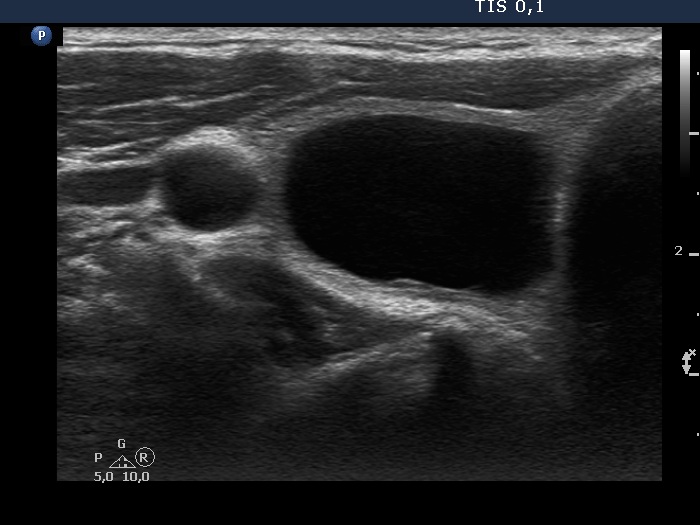

Present examination years after the first examination (third row of images)

Clinical presentation: The patient had no complaints. He noticed a decrease in nodule size.

Palpation: an elastic nodule in the right lobe.

Functional state: euthyroidism (TSH 3.04 mIU/L).

Ultrasonography. Except for the size of the nodule, the pattern remained the same. The dimensions of the nodule were 23x15x33 mm - 5.95 mL.

Suggestion: ultrasound in two years.

At the first examination, the nodule compressed the vessels running outside the nodule while on follow-up this compression was released, therefore the perinodular vascularity became visible.

The nonparallel orientation became parallel.